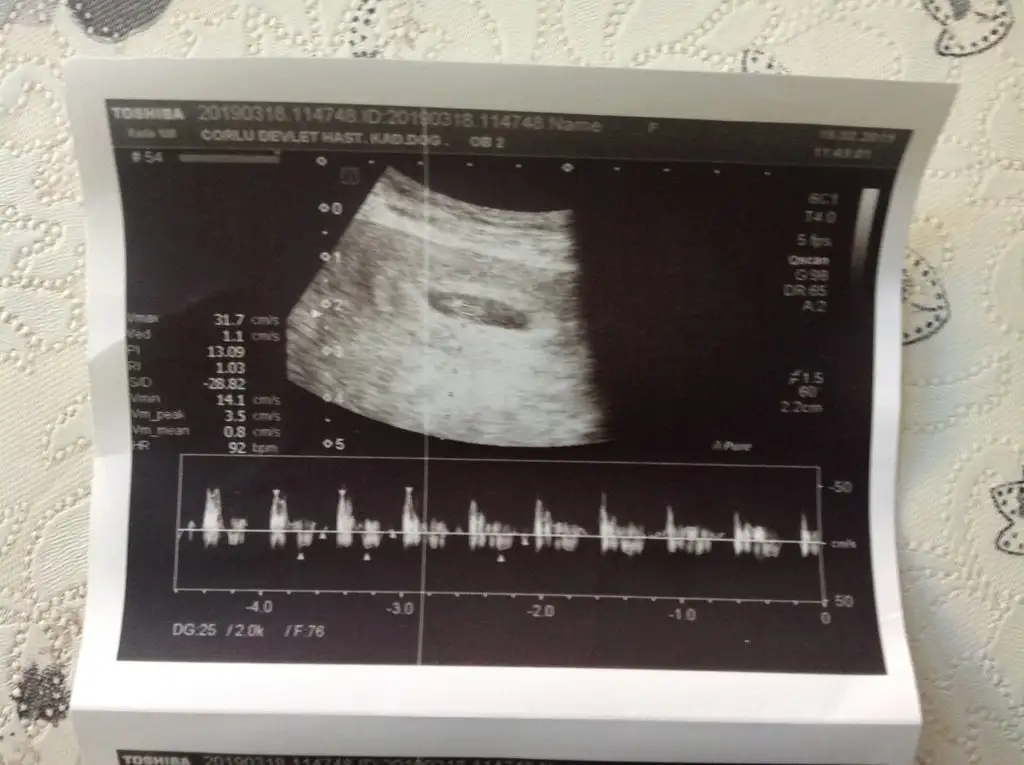

Bi bakarmısınız 7+3günlük

Eklentiler

• 1CF9ED18-666B-4A03-9182-FC4A71AB2706.webp

1CF9ED18-666B-4A03-9182-FC4A71AB2706.webp

44,4 KB · Görüntüleme: 63